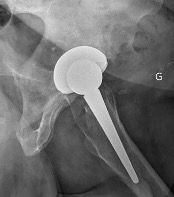

Hips in coxa vara sometimes present a very significant femoral offset which may be prove to be difficult to restore using standard stems. In this case, a varus-tilted or lateralized stem should be used and this will require a very low femoral cut, often with loss of residual femoral offset and a risk of lengthening the lower limb. Positioning a straight cementless stem in varus runs the risk of trajectory error and femoral pain. If a modular neck implant is chosen, the increased lever arm results in significant pressures on the modular neck and neck-head junction with risks that are already known. Finally, even with a cemented stem, positioning it in varus will increase the pressures on the bone-cement interface, with a risk of early loosening. With calcar-guided short stems, the stem will follow the medial cortex of the neck (which will have been cut high), naturally finding a varus tilt and making it possible to reproduce even very significant offsets (Figs 4 and 5).

In our experience, we have not had to carry out any surgical revisions due to failure of the femoral implant. We have come across a few cases of secondary subsidence, with good prosthetic stability with time. The cause of this subsidence seemed to us to be an under-sized implant. We will discuss this in the section on fitting technique.

Planning - The intervention begins before the incision, with the preparation. As Franklin said “If you fail to plan, you are planning to fail”. Pre-operative planning is an integral part of the success of the operation, in that it involves assessing the native hip parameters (which should be restored) and anticipating any peri-operative difficulties. This planning means that the precise size of the final stem can be determined, ensuring optimal intramedullary filling, and the correct height of the femoral neck cut can be identified. Under-sizing risks secondary subsidence, especially in somewhat valgus tilted femurs . Stem positioning must follow the calcar rather than the diaphyseal axis, which will enable the femoral offset to be restored. Restoring an optimal overall offset also depends on the depth to which the socket is burred, as this may sometimes need to be compensated for on the femoral side. Finally, it is important to take femoral torsion into account. All this points to the value of 3-dimensional planning systems that take these parameters into account (EOS or CT scan), and are more complete than the conventional practice of sketching on AP radiographs.